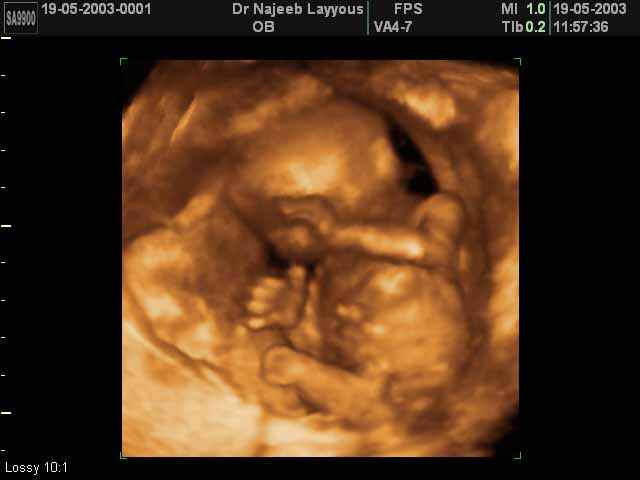

- Fetal Behavior Ultrasound Photos

- Fetal behavior during pregnancy

3D Second Trimester Ultrasound Scan Photos-second part of pregnancy | Dr N Layyous